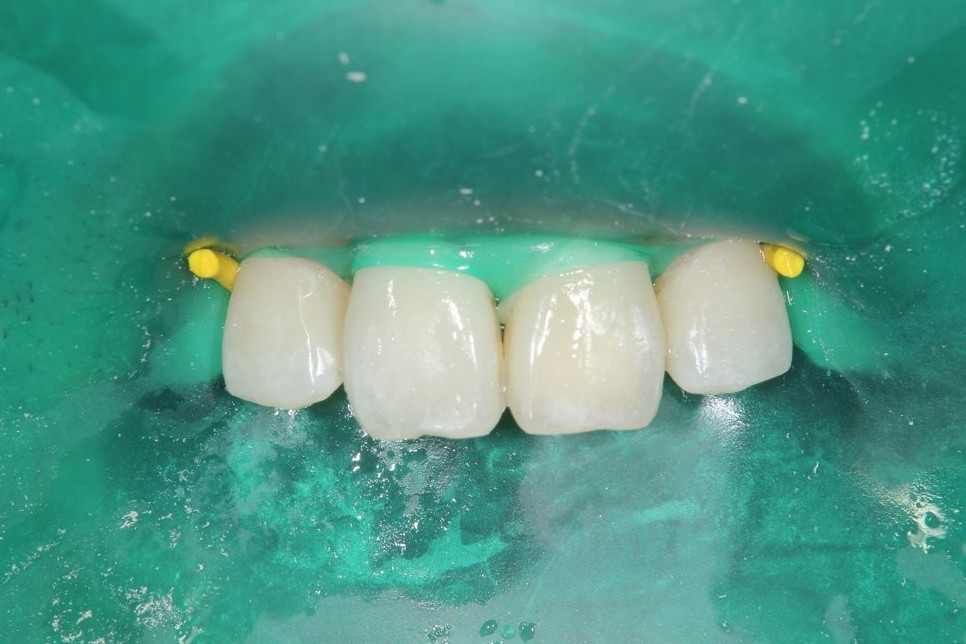

前歯の虫歯です。唾液の量が多い方や歯ぐきから出血がある方にはラバーダム防湿法を使います。このように緑色のゴムのシートを使用して、歯に唾液や血液が付かない様にします。

虫歯をとったところです。

無事治療が終わりました。削った穴に唾液や血液が入り込むと接着力が低下してしまいます。今回、削った穴に汚れが付く事無く、審美的な治療が出来ました。

ダイレクトボンディング

費用2万円×2本

リスクとして変色や欠ける可能性がある(修復可能)。